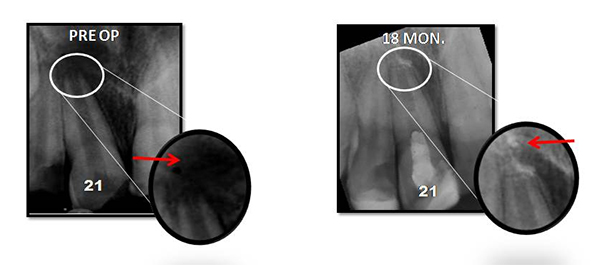

Tanisha Konai -

PRP Mediated REP in 21 with 18 months follow up

Bone healing, Apical PDL formed, Apex Closed, Calcific Bridge formed in 21.

Vitality Positive